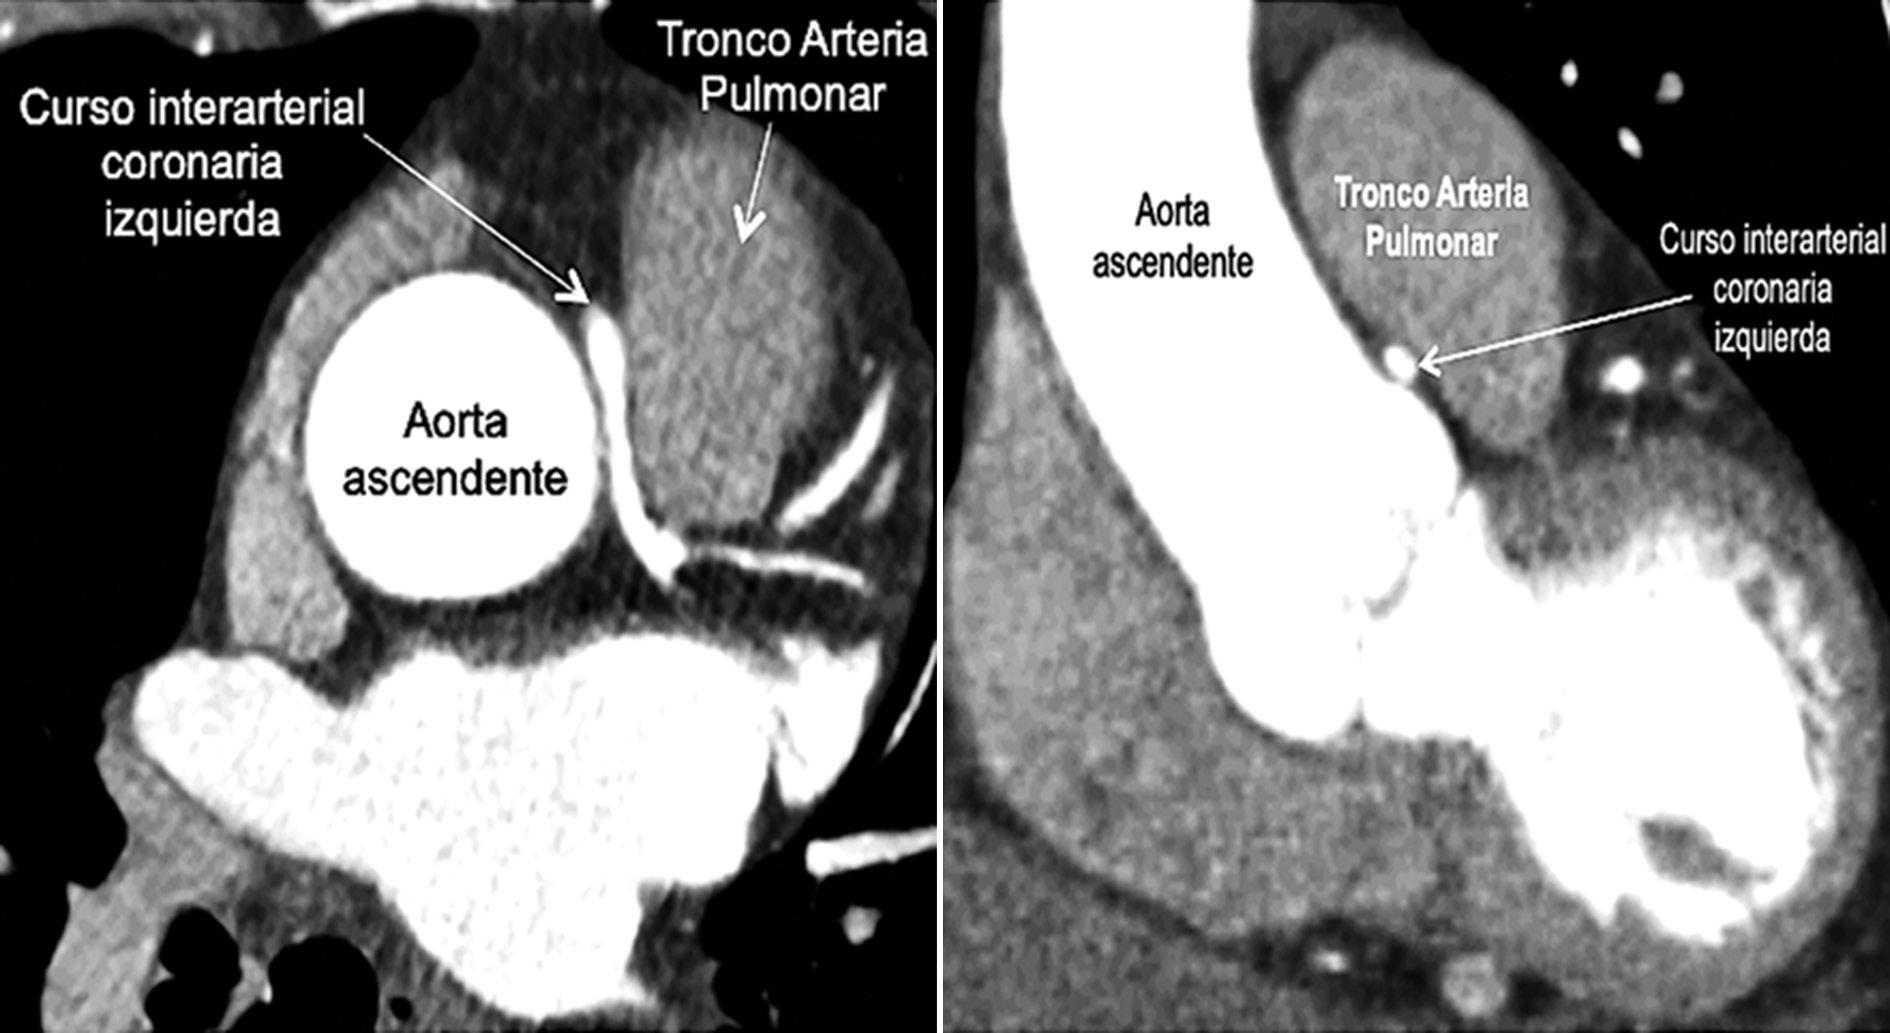

Figura 1 Corte axial y coronal que muestran salida del tronco izquierdo desde el lado derecho y curso entre arteria pulmonar y aorta hacia el ventrículo izquierdo.

Paciente de 77 años que consulta por dolor torácico de 10 meses de evolución que se había agudizado en la última semana, opresivo, retroesternal, en reposo y en ocasiones con el ejercicio, asociado a mareo. Se consideró sospecha de síndrome coronario agudo, electrocardiograma (ECG) normal, las troponinas descartaron infarto de agudo de miocardio y por situación pandémica y exposición del paciente también se descartó infección por coronavirus 2 del síndrome respiratorio agudo grave (SARS-CoV-2). Se hizo diagnóstico de angina inestable de bajo riesgo, se estratificó con ecocardiograma de estrés con ejercicio negativa para isquemia, con fracción de eyección conservada, insuficiencia aórtica leve a moderada y reporte de una dilatación de aorta a nivel de senos de Valsalva de 5 cm. Por este último hallazgo y no tener clara la etiología del dolor torácico se realizó angiotomografía (angio-TC) de aorta (Fig. 1), en la cual se encontró una dilatación leve de la aorta ascendente con un diámetro 4.1 X 4.1 cm, además se encontró un origen anómalo de las arterias coronarias (OAAC) de la coronaria izquierda (CI) desde el seno Valsalva derecho con curso «maligno» interarterial entre aorta y pulmonar, con un segmento de 12 mm con estrechamiento en el tercio medio de 2.5 mm comparado con 4.5 mm del segmento normal. Pensando en una potencial cirugía, se realizó coronariografía, sin observarse lesiones obstructivas, y aortografía, con insuficiencia grado I/IV; además, nueva ecocardiografía transtorácica que confirmó diámetro máximo de la aorta de 4 cm e insuficiencia aórtica leve. Luego de una amplia discusión multidisciplinaria se decidió realizar cirugía para translocación de arteria pulmonar (Lecompte). Cirugía realizada con éxito, como complicación una fibrilación auricular posquirúrgica que se resolvió en pocos días. Tuvo evolución lenta hacia la mejoría y fue dado de alta en buenas condiciones, asintomático, al séptimo día posquirúrgico. La evolución a los tres meses posquirúrgicos demuestra que continúa con resolución completa de sus síntomas, sin nuevas consultas por urgencias ni hospitalizaciones.

El OAAC es una anormalidad congénita poco frecuente, con una prevalencia estimada del 1%, siendo el origen de la CI con curso interarterial menos frecuente que el de la arteria coronaria (AC) derecha, con una prevalencia estimada del 0.03%1. La presentación clínica va desde angina hasta muerte súbita, siendo las anomalías coronarias la segunda causa de muerte súbita en atletas jóvenes. Se habla de origen anómalo cuando la AC se origina en la aorta, pero del seno coronario inapropiado o cuando la AC se origina desde la arteria pulmonar2. Cuando la AC anómala cursa por el surco entre la arteria pulmonar y la aorta se considera que hay un riesgo aumentado de arritmias malignas y muerte súbita, por la posible compresión arterial3. El término maligna se origina de estudios de autopsia en atletas jóvenes, donde el curso interarterial se consideró la causa subyacente de la muerte súbita4. Sin embargo, este no es el único factor considerado de mal pronóstico y no hay muchos estudios sobre la historia natural de los pacientes no tratados con estas anormalidades, de tal manera que el manejo de estos pacientes sigue generando debate5.